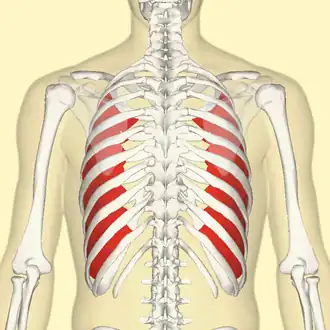

Innermost intercostal muscle (red), seen from back. | |

Innermost intercostal muscle (shown in red). Animation.

Innermost intercostal muscle (shown in red). Animation. -